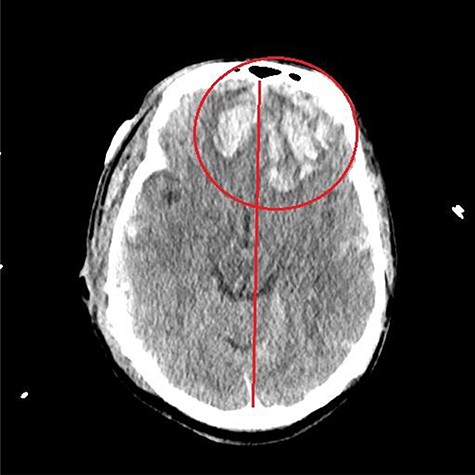

He had a significant recovery, to the point where he was awake with mild right paresis. He was following commands briskly but remained nonverbal. On hospital day 26, he developed neurological deterioration with decreased mental status and worsening right hemiparesis. Clinical examination noted pronounced new indentation of his hemicraniectomy flap site. CT head showed a rightward shift away from the craniectomy site and impending herniation (Fig. 4).

CT head POD26 from craniectomy demonstrating findings consistent with SSFS.